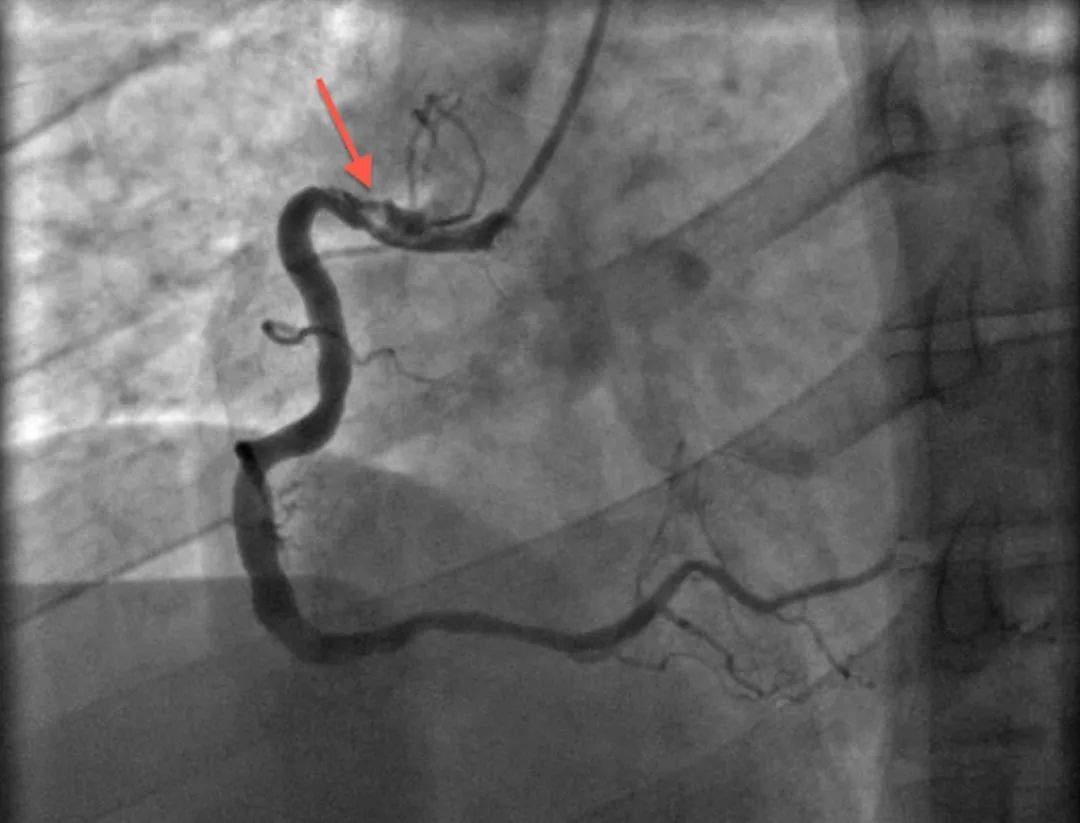

模糊病变陷阱难料?

预规划助力,应对模糊病变游刃有余

迂曲钙化病变

CTO病变